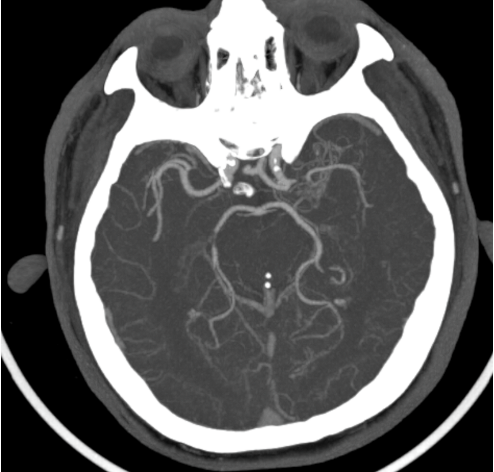

Ngay sau khi bơm thuốc tiêu sợi huyết ghi nhận sức cơ của bệnh nhân Đ. và N. đã cải thiện rõ rệt. Từ kết quả chụp CT mạch máu được thực hiện ngay sau bơm thuốc tiêu sợi huyết (Hình 2 và Hình 4) thấy cục huyết khối đã tiêu, tuy nhiên vẫn có sự hẹp của một động mạch lớn nội sọ ở cả 2 trường hợp.

| Hình ảnh hẹp động mạch não giữa trái đoạn M1 của bệnh nhân N.V.Đ - Ảnh BVCC |